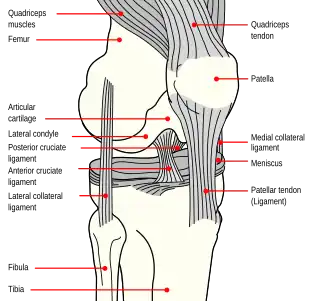

Схема правого колена. | |